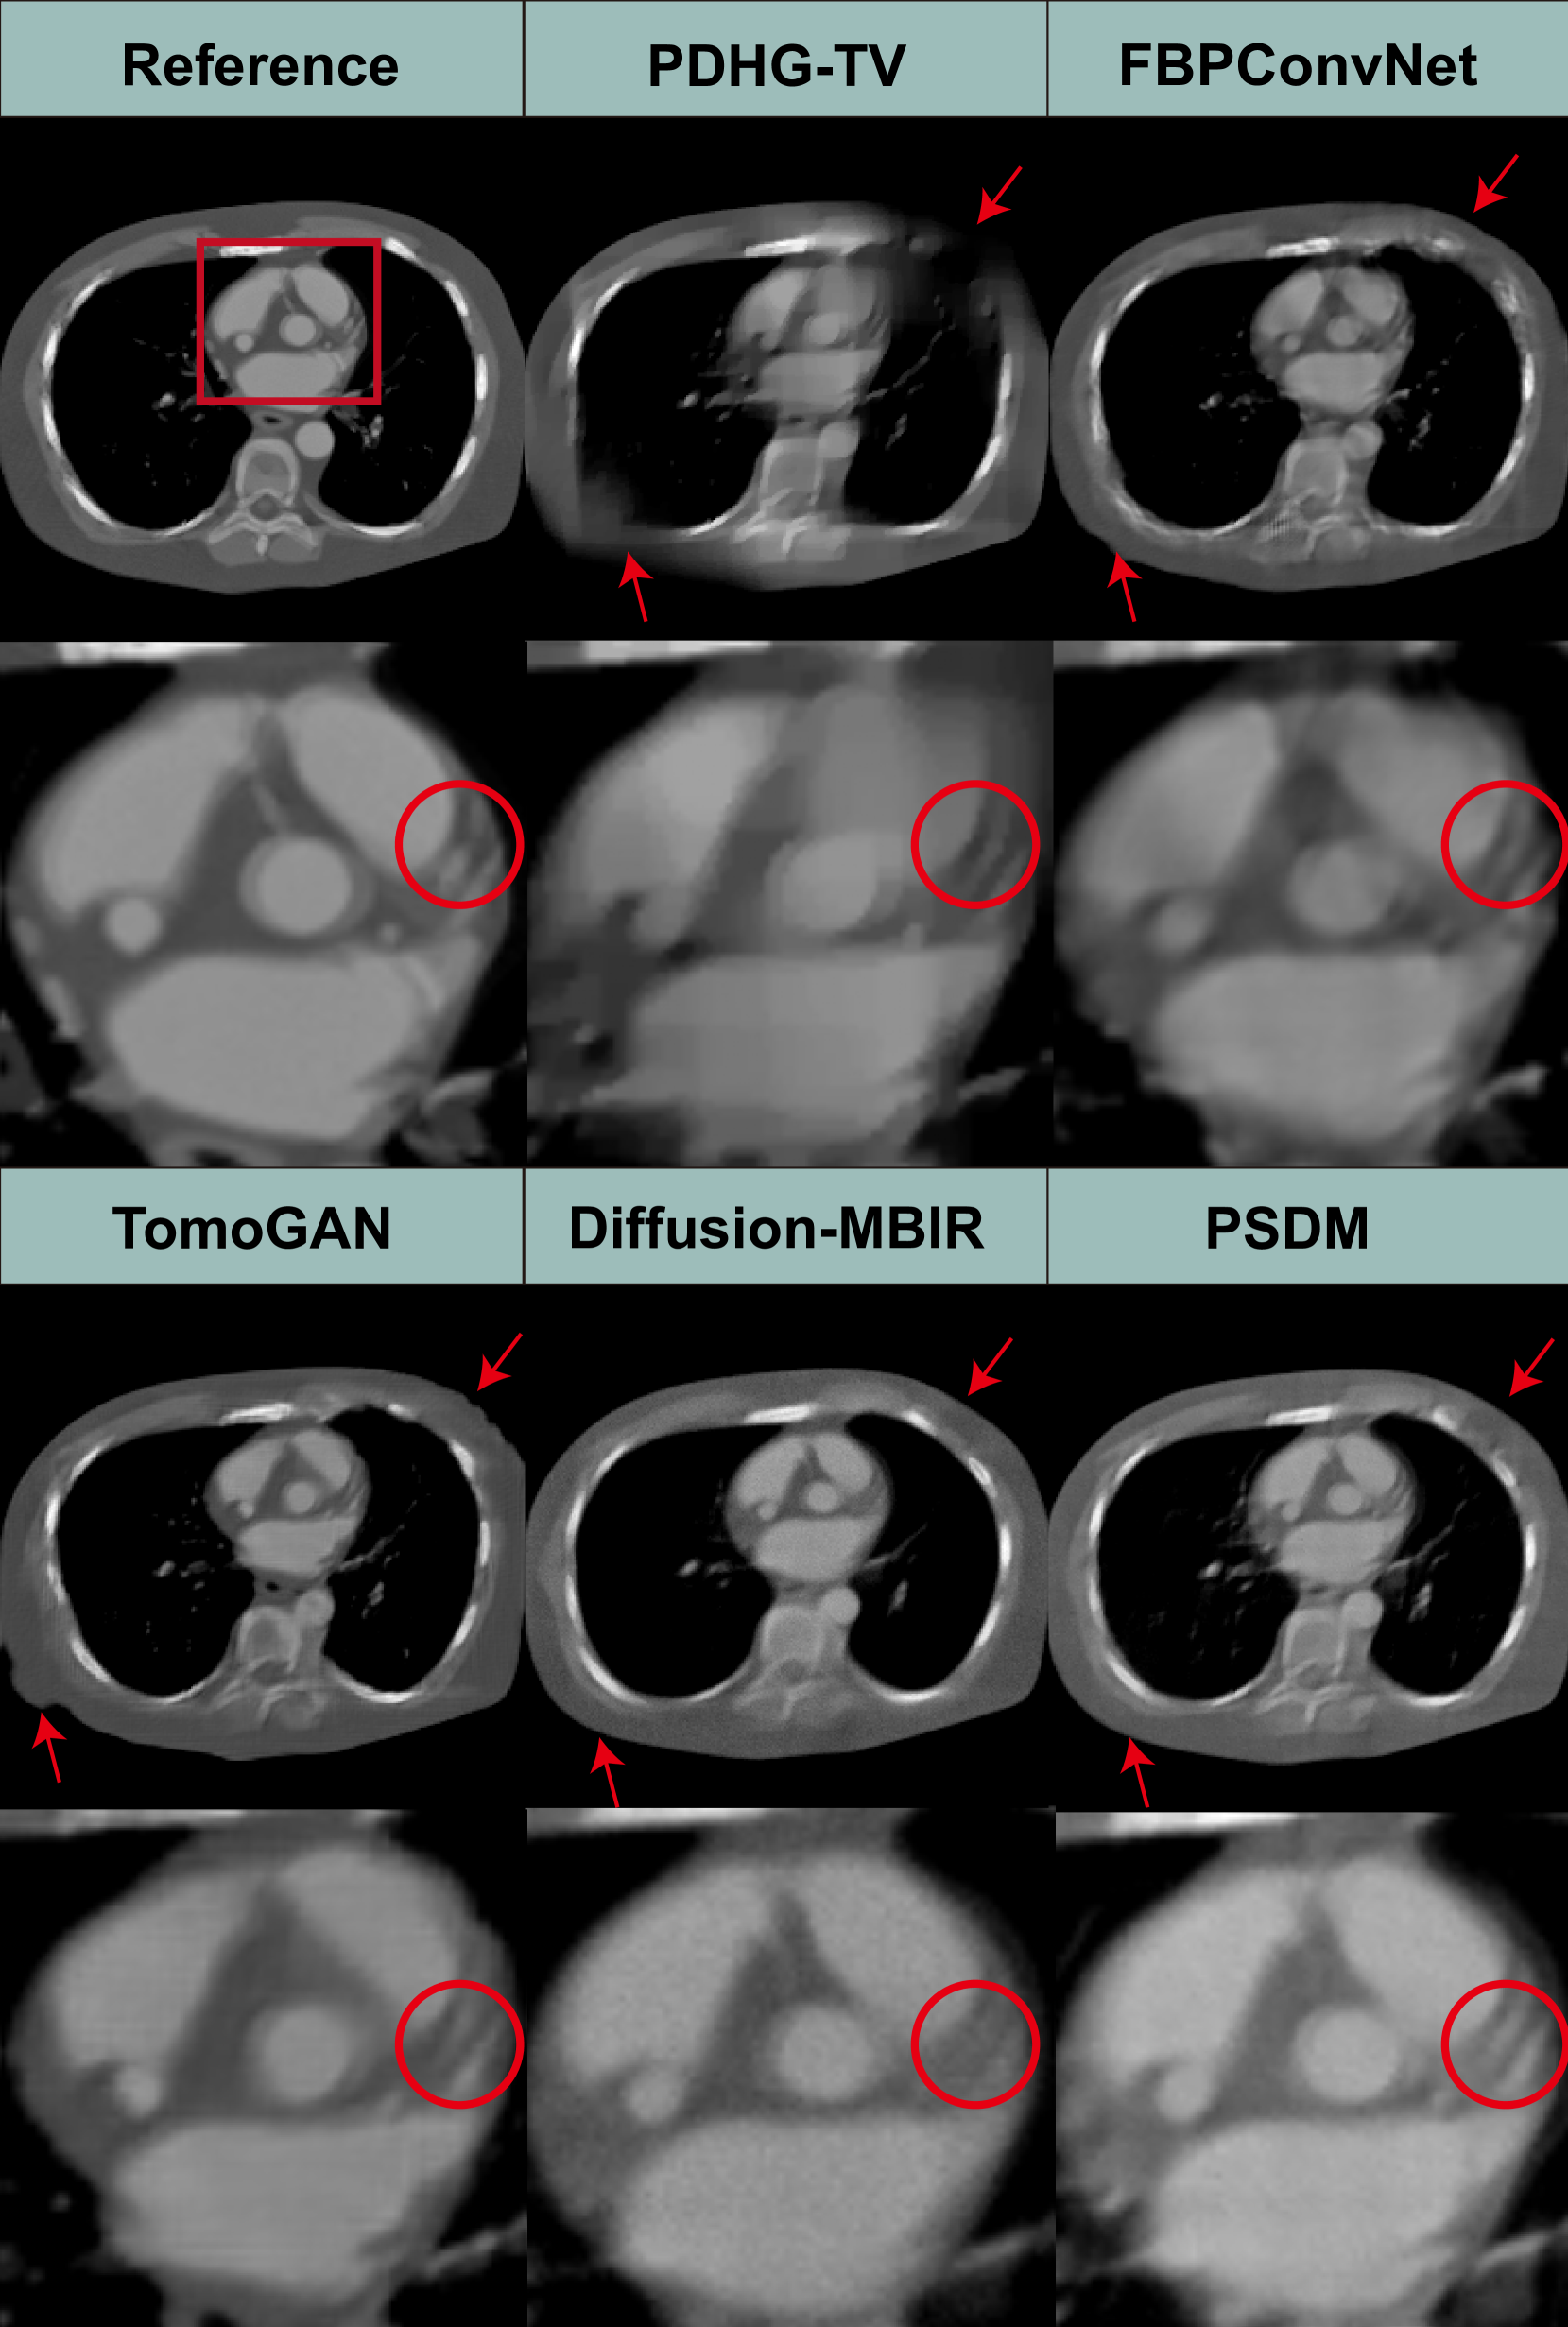

Refer to caption

Figure 6: Reconstruction results from a clinical cardiac CT scan, using different methods, each corresponding to different scanning angular ranges of 120°. The first row are reconstructions from spanning angles 0° to 120°, the second row are for 30° to 150°, and the third row are for 60° to 180°. The display window is [400400-400- 400 1500150015001500] HU.

4.2.2 Clinical cardiac results

Generalization is a major issue for DLR-based methods, especially for models requiring supervised learning. If a model is trained strictly on data with a specific angle range (e.g., 0–120°), it will not generalize well to other angular ranges. However, different clinical situations might require different angular ranges. For instance, certain anatomical regions or pathologies are better visualized with a specific angle range. To further demonstrate the advantages of PSDM, the algorithm is applied to a real clinical cardiac dataset. With the approval of the Institutional Review Board of the University of Massachusetts, Lowell, a deidentified clinical cardiac CT dataset is obtained from a GE HD 750 scanner. The patient was scanned using axial mode. 1,520 projections are acquired over an angular range of 556° (\approx 1.54 rotations). Each projection row has 835 elements at 1.095 mm pitch. The source to the rotation center distance is 538.5 mm, and the source to the detector distance is 946.7 mm. Reconstruction is performed by FBP using equi-angular geometry, where the image size is set to 512×512512512512\times 512512 × 512 to accelerate the sampling process. Since the supervised learning-trained models (FBPConvNet and TomoGAN) usually can only process specific angle range, we compare only the two unsupervised learning methods: Diffusion-MBIR and PSDM. During the sampling stage, these two methods directly utilize the checkpoints trained on the aforementioned Stanford AIMI COCA datasets. Fig. 6 shows the 120-view limited-angle reconstruction images from different angular ranges. We find that both Diffusion-MBIR and PSDM produce consistent and apparently acceptable results. However, compared with the Diffusion-MBIR, the results produced by PSDM exhibit fewer limited-angle artifacts and appear to provide a more realistic representation. These differences can be seen in the areas and structures underscored by red circles and arrows. Specifically, in the atrial region denoted by the red arrow, PSDM produces more stable results, while Diffusion-MBIR still exhibits limited-angle artifacts in the atria.